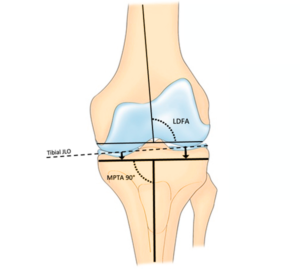

This well-established technique involves placing the knee implant in a straight, neutral position, typically perpendicular to the mechanical axis of the leg. It remains a widely used method that may be suitable for patients with severe deformities caused by arthritis or trauma. Mechanical alignment aims to evenly distribute forces across the joint and enhance long-term implant durability.

Kinematic alignment is a more personalised technique that aims to match the natural shape and motion of your knee before it was affected by arthritis. By preserving your natural joint line and soft tissue balance, this method may feel more natural during movement and daily activities.

The choice of implant materials, sizes, and design features is determined by several factors including your bone quality, activity level, and the alignment of your knee. During pre-operative planning, imaging such as X-rays, CT, or MRI scans help your surgeon select and position the components to match your natural anatomy.

Before your surgery, your orthopaedic team will use detailed imaging, such as X-rays and a CT scan, to develop a personalised surgical plan. These scans provide an accurate 3D map of your knee joint, helping identify its shape, alignment, areas of cartilage loss, and how arthritis has affected joint movement. This information allows Prof. Justin Hunt or Prof. Vera Maria Sallen to plan your total knee replacement procedure with a high degree of precision. Key surgical decisions, such as where to make bone cuts, how much bone to remove, and how to position your implant, are made based on your unique anatomy.